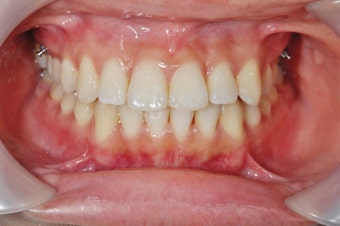

- 임플란트·틀니는 3~6개월마다 정기 검진 필수. 초기 3개월은 적응 기간.

- 임플란트 보철물로 인한 저작 소리나 불편함은 교합 조정으로 해결 가능.

- 자연 치아 vs 임플란트: 자연 치아는 완충 역할을 하는 치주 인대가 있으나, 임플란트는 없어 합병증 발생 위험↑.

- 합병증(나사 풀림, 파절 등)은 초기 자각 어려움 → 정기 검진 필수.